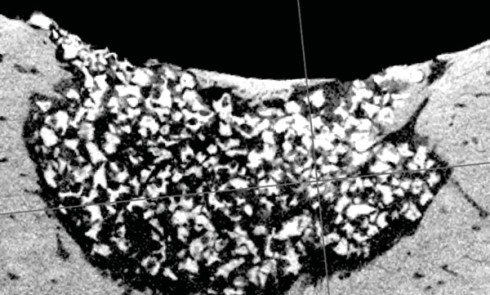

Article réservé à nos abonnés Caractérisation d’un défaut cutanéo-muqueux et osseux chez le minipig avec mise au point d’un protocole de thérapie cellulaire

Si la plupart des dentistes finissent leur parcours par leur thèse d’exercice, d’autres, qu’on appelle alors « doctorants », choisissent de continuer...